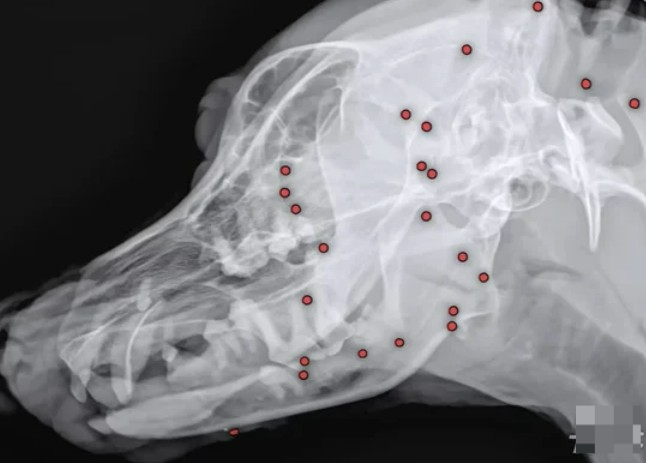

충남의 한 지역에서 백구 한 마리가 몸에 수십 개의 총알을 맞은 채 살아 돌아다니는 사건이 발생했습니다.

동물보호단체에 의해 구조된 이 백구는 현재 병원에서 치료 중이며, 수술을 통해 총알을 제거 중입니다.

더 충격적인 사실은 총알이 공기총이 아닌 산탄총 계열일 가능성이 높다는 점입니다.

누군가 고의로 발사했을 가능성이 커지면서 동물 학대에 대한 국민적 분노가 들끓고 있습니다.